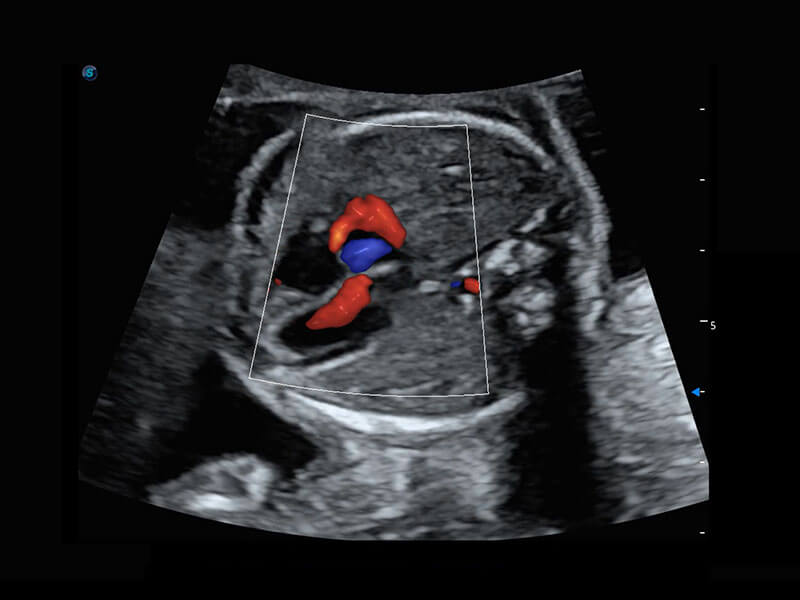

• 四腔心血流

• 胎儿体循环